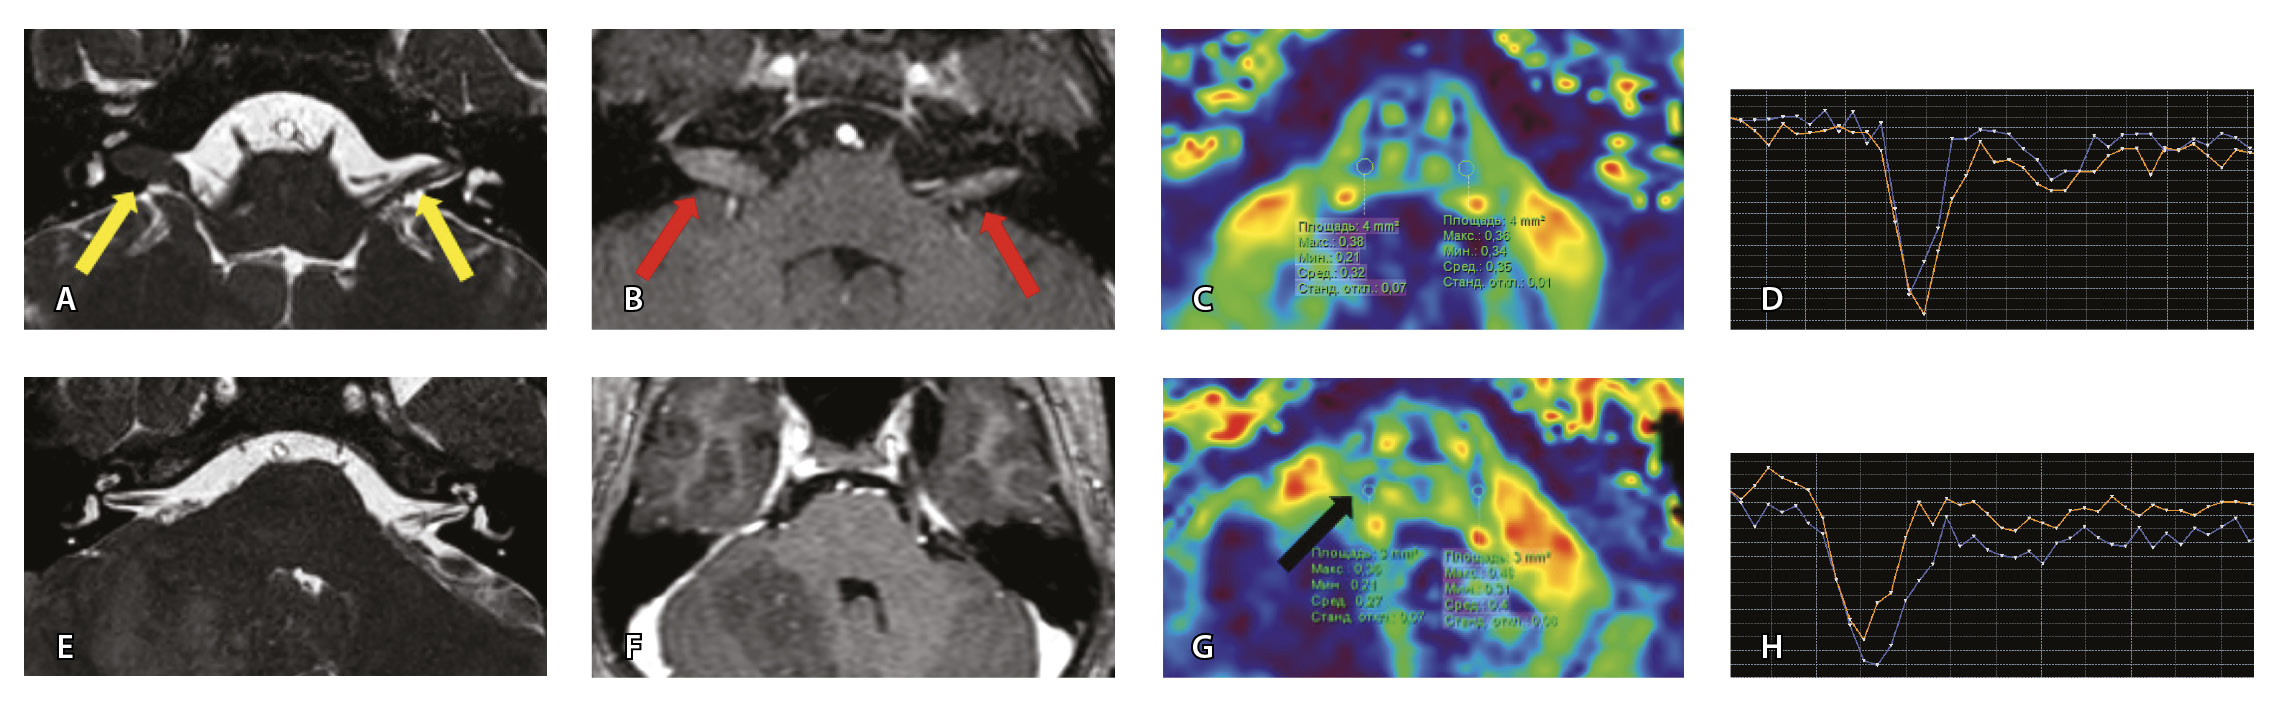

Рис. 7. Клиническое наблюдение 2, пациент 6 лет (А, Б, В, Г). Магнитно-резонансная томография (МРТ) головного мозга: А – прицельная T2-SSFP на область мосто-мозжечкового угла; Б – Т1-взвешенное изображение с контрастным усилением; В – диффузионно-тензорная МРТ (фракционная анизотропия, ФА); Г – Т2*-перфузия. На изображении T2-SSFP отмечается утолщение корешков лицевого, вестибуло-кохлеарного нервов во внутренних слуховых проходах (А, желтые стрелки) и интенсивное накопление ими контрастного вещества (Б, красные стрелки). На уровне моторных ядер лицевых нервов в заднем отделе варолиевого моста значения ФА симметричны (В), признаков гипо-/гиперперфузии не выявлено (Г).

Клиническое наблюдение 3, пациент 13 лет (Д, Е, Ж, З). МРТ головного мозга: Д – прицельная T2-SSFP на область мосто-мозжечкового угла; Е – Т1-взвешенное изображение с контрастным усилением; Ж – диффузионно-тензорная МРТ (ФА); З – Т2*-перфузия. На изображении T2-SSFP патологические изменения на уровне прохождения лицевых нервов во внутренних слуховых проходах не определяются (Д). В медиальном отделе правого полушария мозжечка определяется объемное образование, компримирующее стенку IV желудочка и задний отдел варолиевого моста без признаков васкуляризации (Е). На уровне моторных ядер лицевого нерва в заднем отделе варолиевого моста на изображениях ФА на стороне поражения отмечается минимальное уменьшение показателя ФА до 0,27 (Ж, черная стрелка) и признаки гипоперфузии (З, оранжевый график) по сравнению с контралатеральной стороной (З, синий график)

При этом в клиническом наблюдении № 2 из анамнеза жизни известен ранее установленный диагноз лимфобластного лейкоза в стадии ремиссии. В клиническом наблюдении № 3 значимых анамнестических сведений и данных в пользу атипичного течения ПБ получено не было.

Таким образом, при помощи информации, полученной при проведении МП-МРТ, в обоих случаях был установлен симптоматический характер НЛН, обусловленный развитием неопластических процессов. Оба пациента были направлены в профильные хирургические стационары для проведения дальнейшего лечения.